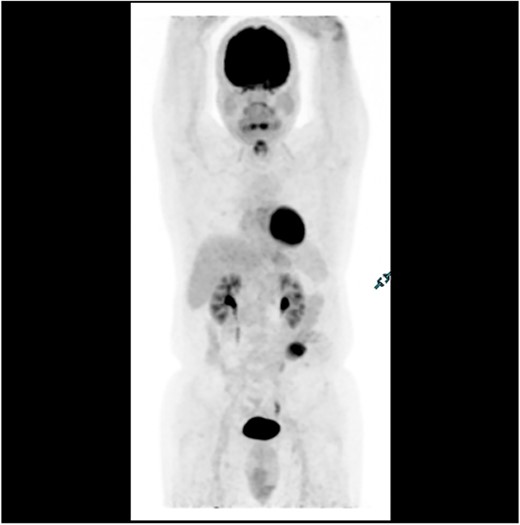

Subsequent surveillance imaging including magnetic resonance imaging and CT scans demonstrated gradual reduction and eventual complete resolution of the liver metastases (refer to Figs 1–4). Furthermore, routine colonoscopy and a positron emission tomography (PET) scan revealed no evidence of locoregional cancer recurrence nor distant metastatic disease present; essentially rendering the patient cured from an initial diagnosis of metastatic rectal cancer. It has been at least a decade since his initial diagnosis and the patient remains in remission.

PET scan in 2018 demonstrating no evidence of FDG avid regional nodal or distant metastasis, especially in the liver.